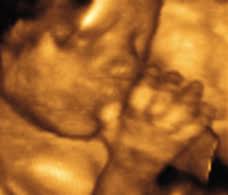

3D / 4D Scan di Malaysia.

POLIKLINIK AL HAFIZ (https://www.facebook.com/poliklinik.alhafiz/)  kini menyediakan perkhidmatan 3D / 4D scan. Imbasan untuk melihat rupa bayi dalam kandungan.

Imbasan / scan 3D/4D adalah seperti gambar tersebut.